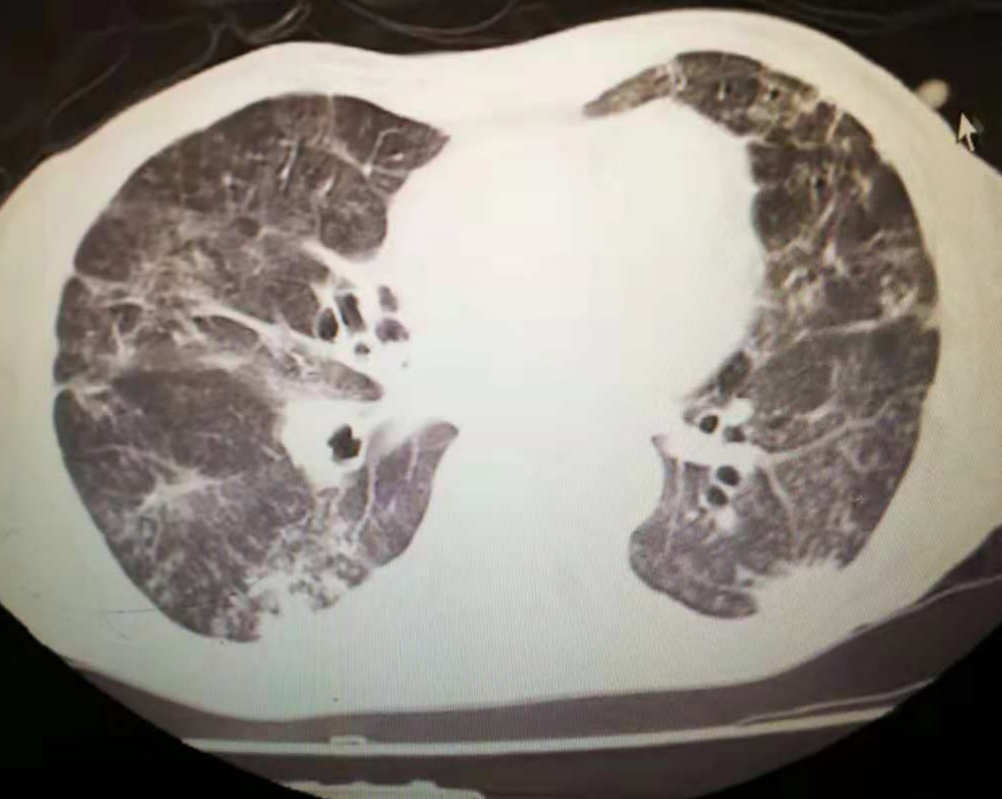

肺里白痰可能是多种肺部疾病的表现。最常见的是支气管炎、肺部感染和慢性阻塞性肺疾病(COPD)。对于这些情况,我们可以通过药物治疗、物理疗法和必要时的手术来缓解症状。